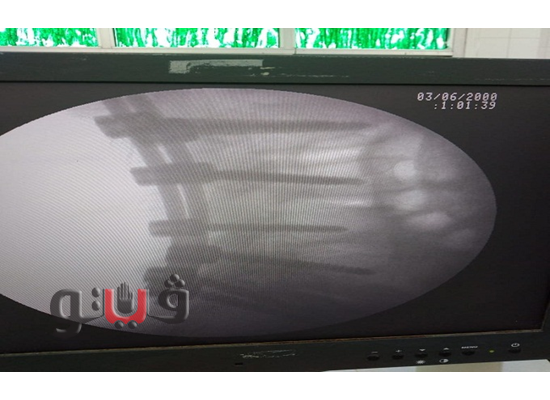

تمكن فريق طبي بمستشفي الصالحية الجديدة المركزي، محافظة الشرقية برئاسة الدكتور أحمد صبري أخصائي جراحة العظام والعمود الفقري، من إجراء عملية جراحية عاجلة لحالة حرجة تحتاج إلي تثبيت إنزلاق غضروفي وإصلاح لإعوجاج بالفقرات القطنية، تحت جهاز الأشعة.

وتمت الجراحة بنجاح والحالة الآن مستقرة وتحت الملاحظة الطبية بالمستشفي، بإشراف مديرة المستشفي.